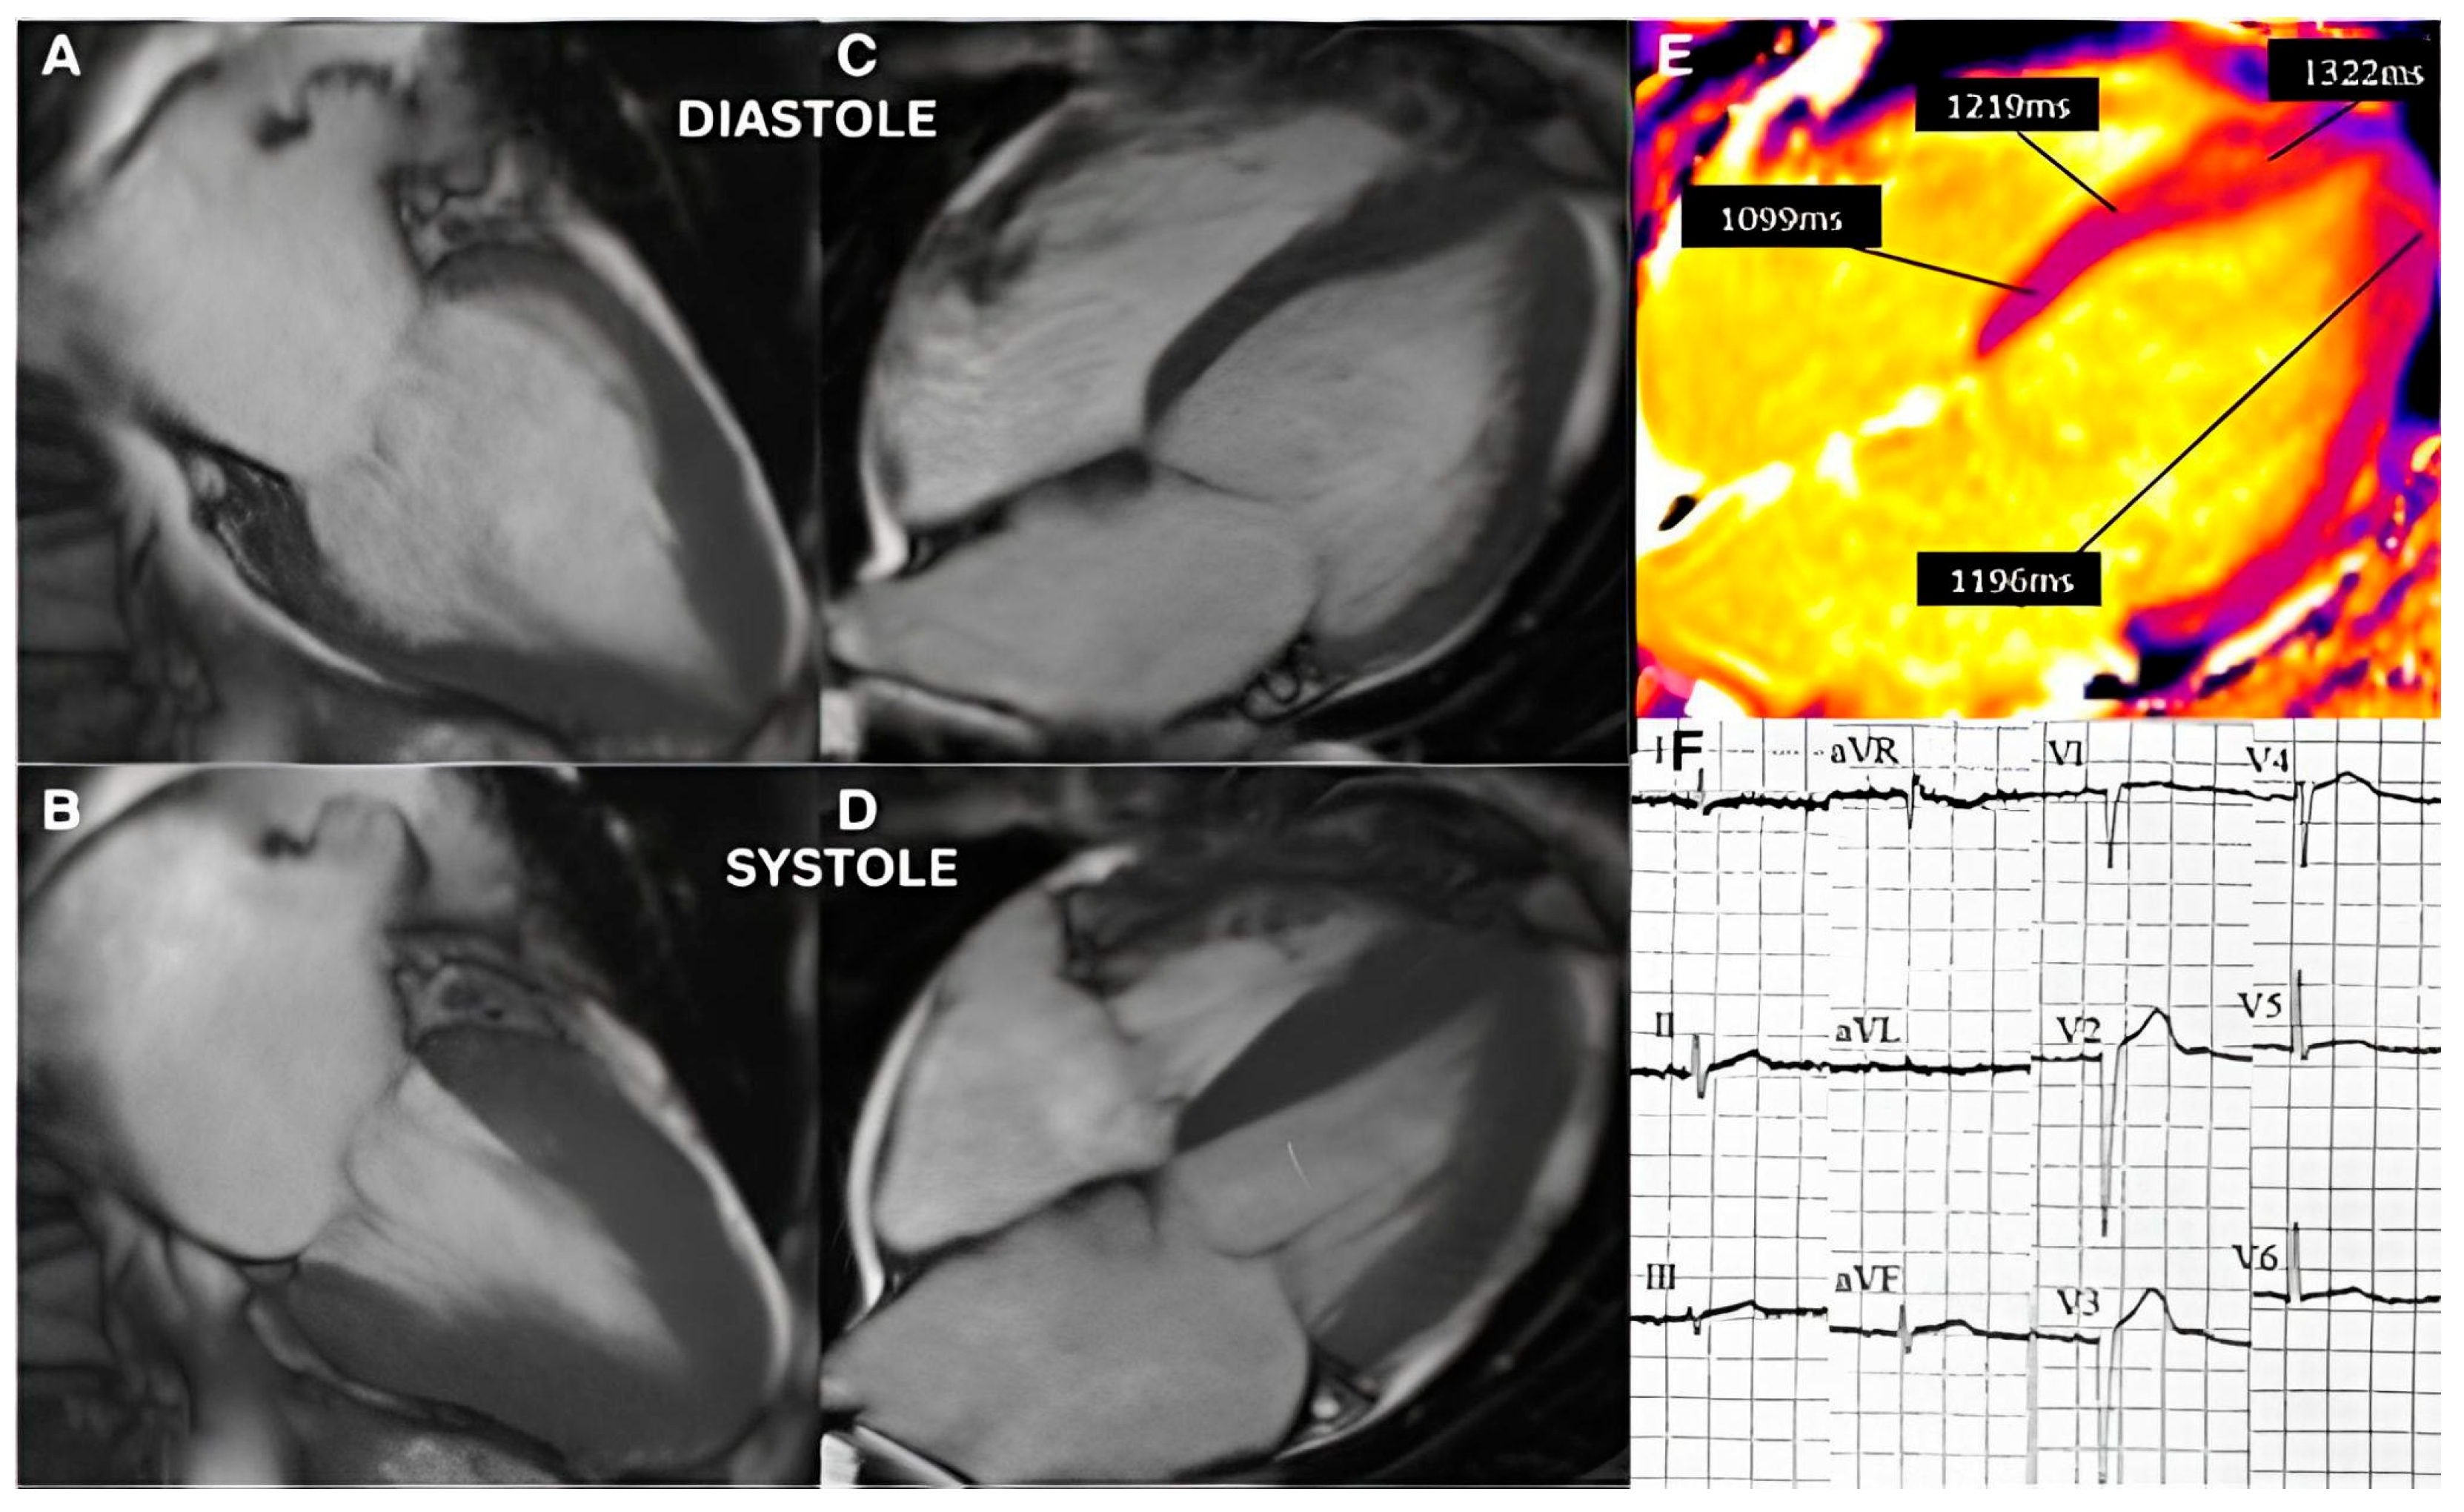

3.2. Imaging and Hemodynamic Observations

3.4. Integration of Acute and Chronic Stress Effects

4.1. Repeated Acute Stress, Takotsubo Cardiomyopathy, and Stressed Heart Morphology

4.2. Perfusion Abnormalities and Segmental Remodeling Under Cumulative Chronic Stress

4.5. Stressed Heart Morphology and Takotsubo Cardiomyopathy Pathophysiological Correlation